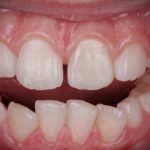

Epulidi gengivali in aree ad alta valenza estetica. Trattamento chirurgico mini-invasivo Premium

Le epulidi gengivali sono lesioni proliferative benigne di natura reattiva che originano dalla gengiva e dal tessuto connettivo sottostante. In questo articolo gli autori descrivono tre casi clinici in cui le epulidi gengivali sono state trattate con successo mediante l'impiego di laser a diodi.